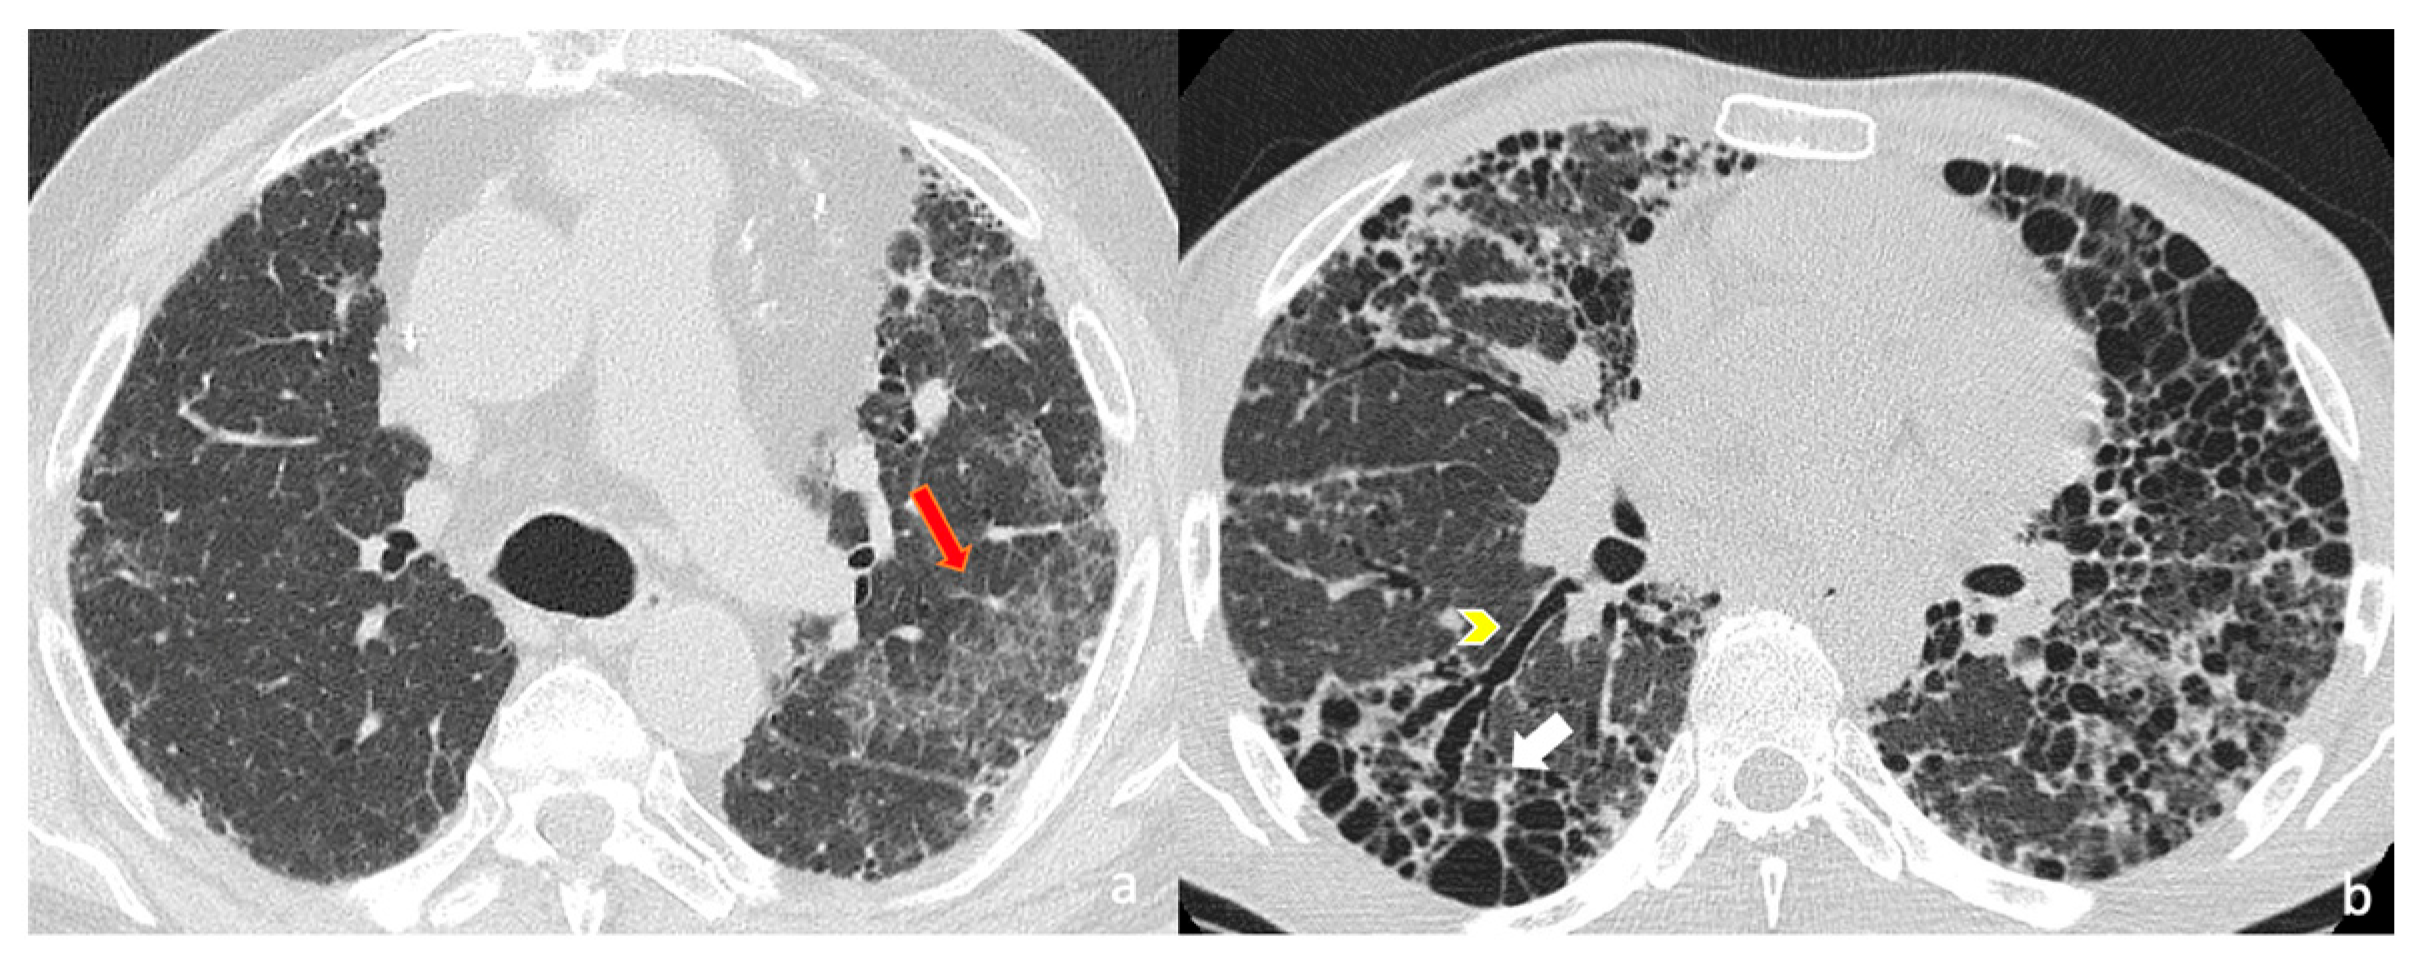

Images were evaluated in consensus. The following imaging findings were assessed: (i) fibrosis distribution (evaluating the cranio-caudal extension and the lung involvement in the and axial plane); (ii) key imaging features of fibrosis, represented by honeycomb, traction bronchiectasis and volume loss; (iii) ancillary imaging findings of fibrosis features—reticulations, ground-glass areas and pulmonary ossifications (Figure 1).

Figure 1. High-resolution computed tomography (HRCT) of the chest in axial (a,b) views. (a) Axial HRCT shows ground-glass opacities (subtle hazy increased attenuation) in left upper lobe, superimposed on fine reticulations (red arrow), suggesting fibrotic interstitial lung disease. (b) Advanced fibrotic changes are evident with traction bronchiectasis (yellow arrowhead) and extensive honeycombing (white arrow) in the posterior basal segments of the lower lobes, characterized by clustered cystic airspaces of similar diameter.